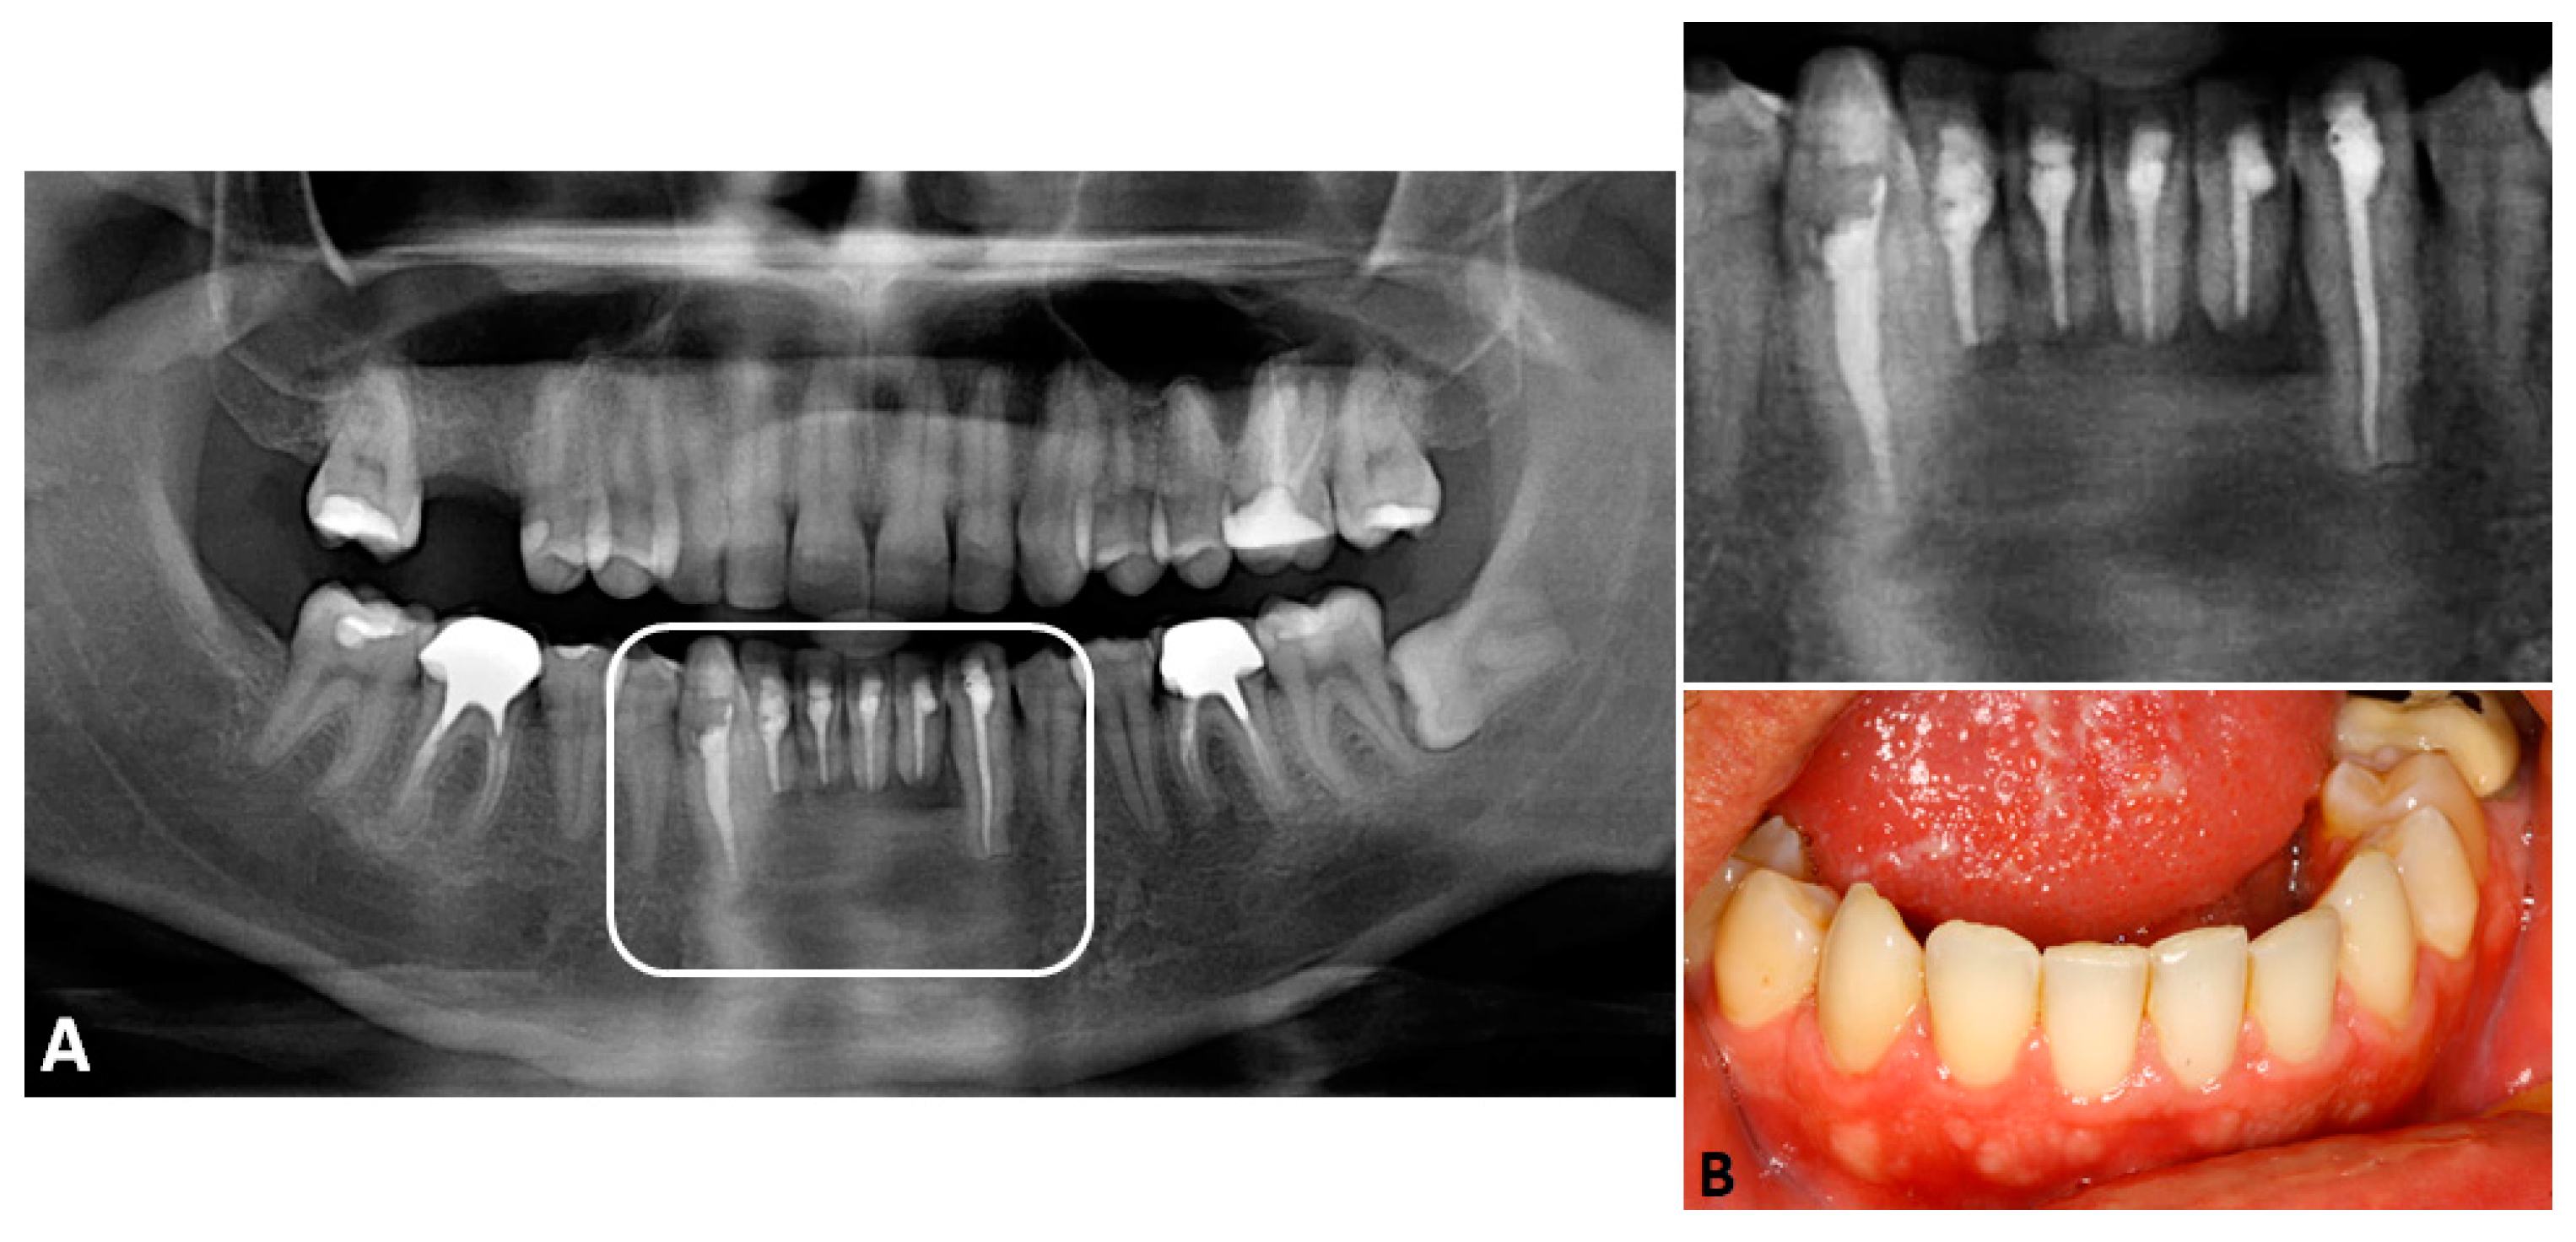

Considering the high recurrence rates of GOC, adequate follow-up appointments were set. Eight months after the first procedure, a recurrence was detected by CT scan in the lingual portion of the cortical bone (Figure 4A,B). The patient underwent a new surgical approach under local anesthesia. The lesion was accessed through an incision at the lingual region—osteotomy and curettage were then performed, as previously described (Figure 4C).

Fifteen months after the second procedure, the panoramic radiograph showed a nearly complete bone neoformation within the surgical site. Clinically, the mucous membranes were found to be intact, with no signs of recurrence. Furthermore, all teeth were in function, without clinical or aesthetic repercussions (Figure 5).

Figure 4. (A)—Representative coronal cut and (B)—sagittal cuts of the CT scan 8 months after the first surgery, revealing recurrent lesions in the apical region, lingually. (C)—Trans-operative image of the second surgical approach, aiming the removal of the recurrent lesion in the lingual portion of the cortex. The arrows point to the recurrent lesions.

Figure 5. Follow-up of fifteen months after the second procedure. (A)—The panoramic radiograph showed bone neoformation within the entire surgical site, with no signs of recurrence. (B)—Clinically, the mucosa was found to be healthy, and the involved teeth were in function, without functional or aesthetic repercussions.